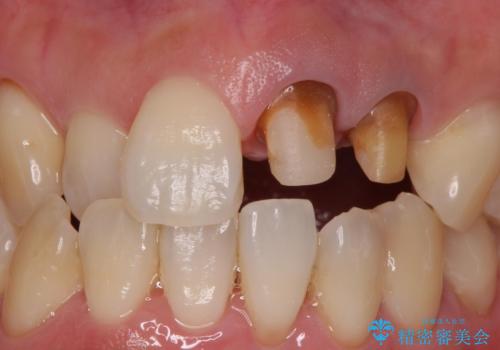

- 前歯の変色を主訴に来院された患者様です。

再根管治療からのやり直しも提案しましたが、特にご希望されなかったためクラウンでの修復処置のみ行います。

歯は根管治療が終了して時間が経つとだんだん茶色く変色していきます。